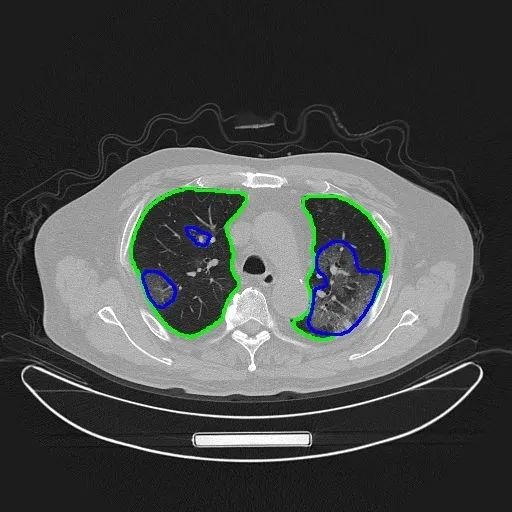

从统计数据看,新冠肺炎患者的核酸检测目前仅30%到40%是阳性,因取样于鼻咽部而非肺部,用CT可以看到肺部被感染的情况,CT可作为辅助诊断手段。一个患者的肺部CT照片有很多张,借助AI可以将肺部的上百张CT照片还原为一幅3D影像。基于对众多新冠病毒感染肺炎患者CT影像的大数据分析,结合AI技术可开发出智能评价系统,帮助医生进行病灶分级,量化评估用时可从常规5个多小时缩短到几分钟。

利用AI技术对CT图像进行自动分割,“腾讯觅影”AI专用CT设备最快2秒即可完成新冠肺炎识别,相关设备已在湖北进行部署。上图中,绿色圈是肺部,蓝色圈是新冠肺炎病灶。